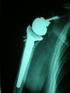

18 RADIOGRAFÍA POST OPERATORIA ARTRITIS FRACTURA 18